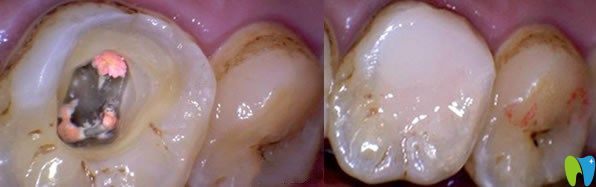

急性牙髓炎主要是細(xì)菌感染引起牙髓組織的急性炎癥,遇冷更加疼痛。急性牙髓炎發(fā)病急,疼痛劇烈,牙齦紅腫、化膿等癥狀,一般鎮(zhèn)痛藥物效果不明顯,遇到良心牙醫(yī)會(huì)保存活髓及患牙,利用開(kāi)髓及藥物來(lái)緩解疼痛,服用消炎藥兩到三天,疼痛緩解后,嚴(yán)重的牙髓炎可采取根管治療或者活髓切斷術(shù),能夠及時(shí)預(yù)防病情嚴(yán)重及擴(kuò)散。沒(méi)有保存價(jià)值的牙齒可拔掉。

急性牙髓炎治療方法